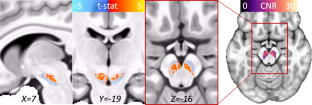

Obsessive-compulsive disorder (OCD) is an impairing psychiatric condition, which often onsets in childhood. Growing research highlights dopaminergic alterations in adult OCD, yet pediatric studies are limited by methodological constraints. This is the first study to utilize neuromelanin-sensitive MRI as a proxy for dopaminergic function among children with OCD. N = 135 youth (6–14-year-olds) completed high-resolution neuromelanin-sensitive MRI across two sites; n = 64 had an OCD diagnosis. N = 47 children with OCD completed a second scan after cognitive-behavioral therapy. Voxel-wise analyses identified that neuromelanin-MRI signal was higher among children with OCD compared to those without (483 voxels, permutation-corrected p = 0.018). Effects were significant within both the substania nigra pars compacta (p = 0.004, Cohen’s d = 0.51) and ventral tegmental area (p = 0.006, d = 0.50). Follow-up analyses indicated that more severe lifetime symptoms (t = −2.72, p = 0.009) and longer illness duration (t = −2.22, p = 0.03) related to lower neuromelanin-MRI signal. Despite significant symptom reduction with therapy (p < 0.001, d = 1.44), neither baseline nor change in neuromelanin-MRI signal associated with symptom improvement. Current results provide the first demonstration of the utility of neuromelanin-MRI in pediatric psychiatry, specifically highlighting in vivo evidence for midbrain dopamine alterations in treatment-seeking youth with OCD. Neuromelanin-MRI likely indexes accumulating alterations over time, herein, implicating dopamine hyperactivity in OCD. Given evidence of increased neuromelanin signal in pediatric OCD but negative association with symptom severity, additional work is needed to parse potential longitudinal or compensatory mechanisms. Future studies should explore the utility of neuromelanin-MRI biomarkers to identify early risk prior to onset, parse OCD subtypes or symptom heterogeneity, and explore prediction of pharmacotherapy response.